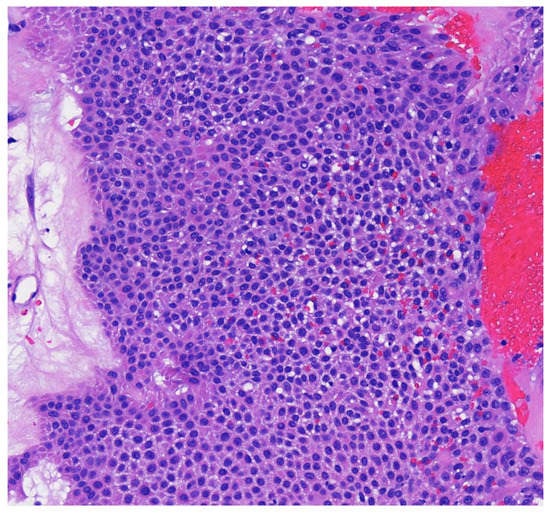

Figure 4. Higher magnification reveals small poriod cells with round to oval nuclei and scant cytoplasm. Ductal lumen formation is present (H & E, 10×).

Poroma variants are differentiated based on the predominant cell type present and the degree of epidermal/dermal involvement [2]. However, multiple variants can exist within the same lesion. DDTs are primarily confined to the superficial dermis and are composed of small solid and cystic nodular aggregates of poroid, cuticular, and clear cells (Figure 3, Figure 4 and Figure 5) [2]. Eccrine poromas are also composed of all three cell types, but are primarily located in the epidermis and superficial dermis. Hidroacanthoma simplex is mainly composed of poroid cells, less cuticular cells, and no clear cells [2]. It is confined to the epidermis. Poroid hidradenoma contains a mixture of all three cell types and is also confined to the dermis [2]. In contrast to DDT, poroid hidradenomas have large aggregates of solid and cystic components and extend deeper into the reticular dermis and even subcutis [2].

The histopathologic diagnosis of DDT is rare due, in part, to the fact that some regard DDTs as poromas with a limited epidermal connection that has not been identified on the histologic sections examined or as hidradenomas that are smaller and more superficial [30]. As an example, Figure 3 may be regarded by some as representing a hidradenoma. This controversy in the histopathologic classification of poroid neoplasms without clear-cut evidence for the clinical significance of distinguishing these lesions from each other has given rise to the thinking that the poroma classification scheme may just be a matter of semantics [19]. This has led to some pathologists diagnosing these lesions under the overarching term as “acrospiroma” only without further classification.